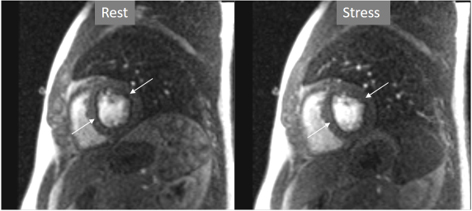

Particularly important, in practice, is the issue of perfusion studies in patients with previous MI. In theory, a basal rest perfusion study should exhibit a reduced signal intensity in the infarcted area, as is the case in the acute phase of a large transmural MI (Fig. 14A). However, not infrequently, the presence and extent of a rest perfusion defect does no correlate with the actual area of necrosis in either, acute (Fig. 14B) or chronic MI (Fig. 15). Signal intensity in areas of previous MI is thus, not dependent merely on the presence of scar tissue, but some other factors lead to differences in CA concentration between MI and remote regions and, in this sense, rest perfusion CMR cannot be equated to SPECT studies, where rest defects are directly related to the presence of infarcted myocardial tissue not amenable to radiotracer uptake [45].

Fig. 14.Rest perfusion after acute myocardial infarction. (A) Frames from different sequences in a case of acute MI showing, from left to right, (1) gross transmural defect at the rest perfusion study (arrow); (2) signs of regional myocardial edema at STIR T2, with a mid-line low intensity region which proves to be due to (3) intramural hematoma at T2* sequence; (4) persistence of hypoperfusion at Early Gadolinium Enhancement (EGE); and (5) transmural anteroseptal necrosis with a subendocardial area of microvascular obstruction (arrow). (B) The same series of sequences in another patient with AMI showing (1) mild subendocardial defect at rest (arrow); (2) regional edema; (3) absence of hematoma at T2*; (4) lack of persistent defect at EGE; and, finally, (5) a transmural infero-lateral LGE (arrow) without microvascular obstruction.